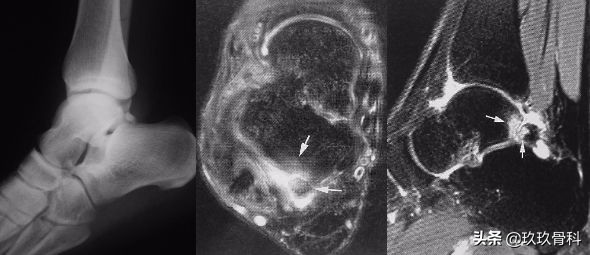

距后三角骨损伤

距骨后突延长

第二距骨损伤

距后三角骨、第二距骨损伤▲▲▲

解剖:外结节、内结节

受伤机制:足剧烈跖屈损伤

病理:末端病表现

症状及诊断:跖屈痛、屈拇长肌腱炎

治疗:封闭、制动、手术

鉴别:跟距后关节骨关节病;第二距骨损伤